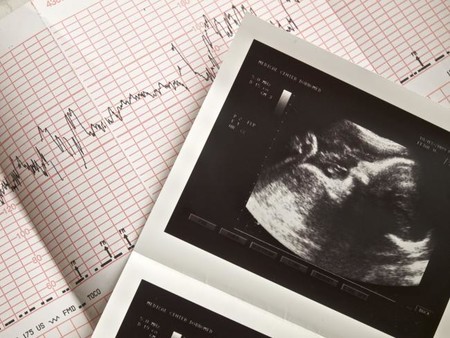

Ecografía del tercer trimestre

Ecografia

La ecografía del tercer trimestre tiene lugar entre las semanas 32 y 36, y es muy útil para valorar el estado del bebé, la placenta y el líquido amniótico, así como para descartar posibles anomalías.

Con esta prueba de ultrasonido se verá también la posición del bebé y se calculará su peso aproximado con las medidas del diámetro cefálico, el diámetro abdominal y el largo del fémur. Con esto se comprobará que el desarrollo es correcto y no hay crecimiento intrauterino retardado (CIR).

Si en esta ecografía tu médico te dice que tu bebé no está bien colocado, no te alarmes. Todavía quedan algunas semanas por delante para conseguir que se gire y se coloque correctamente para nacer.

Monitorización fetal

Monitores

La monitorización fetal antes del parto es una prueba prenatal indolora que se realiza para controlar el bienestar del bebé al final del embarazo. Generalmente se hace a partir de la semana 37 o 38, y mide tanto el latido cardiaco del bebé, como la actividad uterina de la embarazada.

En la mayoría de los casos, la prueba de monitores suele tener una periodicidad semanal, y aunque hay madres que pasan por ella varias veces antes del nacimiento de su bebé, otras no llegan a realizársela porque se ponen de parto antes.